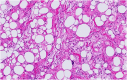

Methods: A 39-year-old man presented with signs of spinal cord compression for the past 2 weeks. His medical history was consistent for an asymptomatic right iliac wing mass that appeared 3 years ago and for which he has not consulted. Magnetic resonance imaging revealed multiple bony lesions of the thoraco-lumbar spine associated with a 6-cm right paravertebral mass at the T4 level extending posteriorly through the intervertebral foramina to the spinal canal causing major spinal cord compression. An emergent T2-T6 laminectomy allowed for a complete resection of the epidural mass. Pathological examination confirmed the diagnosis of well-differentiated liposarcoma. Adjunctive radiation therapy was administered.